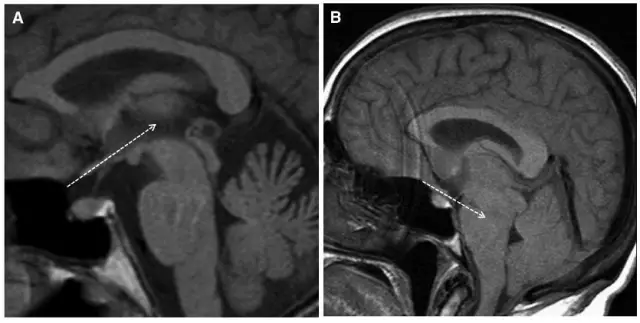

但术后2天再次出现头痛,不能缓解,5月2日复查头颅MRI提示硬膜下血肿术后复发,伴小脑下坠,脑沟及小脑上方仍可见较多脑脊液,四脑室变小,颅内静脉系统扩张明显(箭头所示见横窦扩张)(图3)。

图3. 术后1周(5月2日)复查头颅MRI显示左侧硬膜下血肿术后复发,伴小脑下坠,脑沟及小脑上方仍可见较多脑脊液,四脑室变小,颅内静脉系统扩张明显(箭头所示见横窦扩张)。